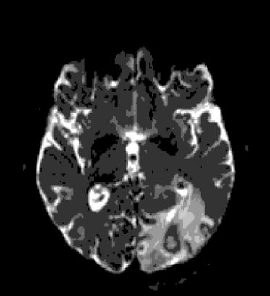

Uma ressonância magnética com contraste do cérebro revelou uma lesão em anel de 16 mm no lobo

occipital esquerdo, rodeado por edema. O paciente foi tratado com Levetiracetam e transferido para o